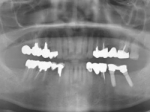

術前レントゲン